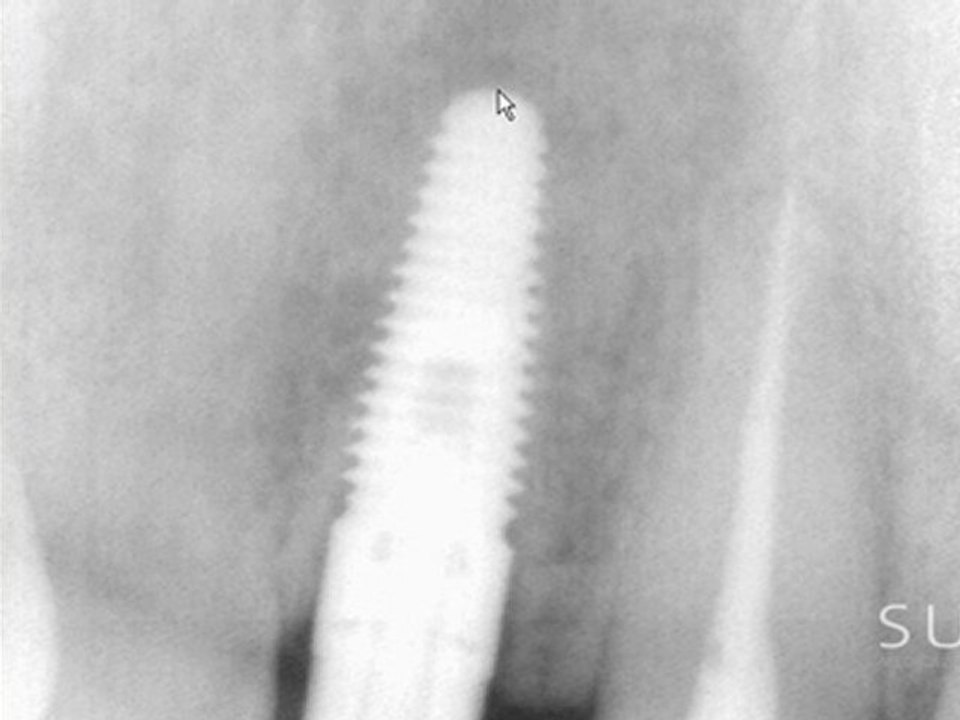

Intraoral Case Studies Imaged with Suni Sensors: Chapter 4